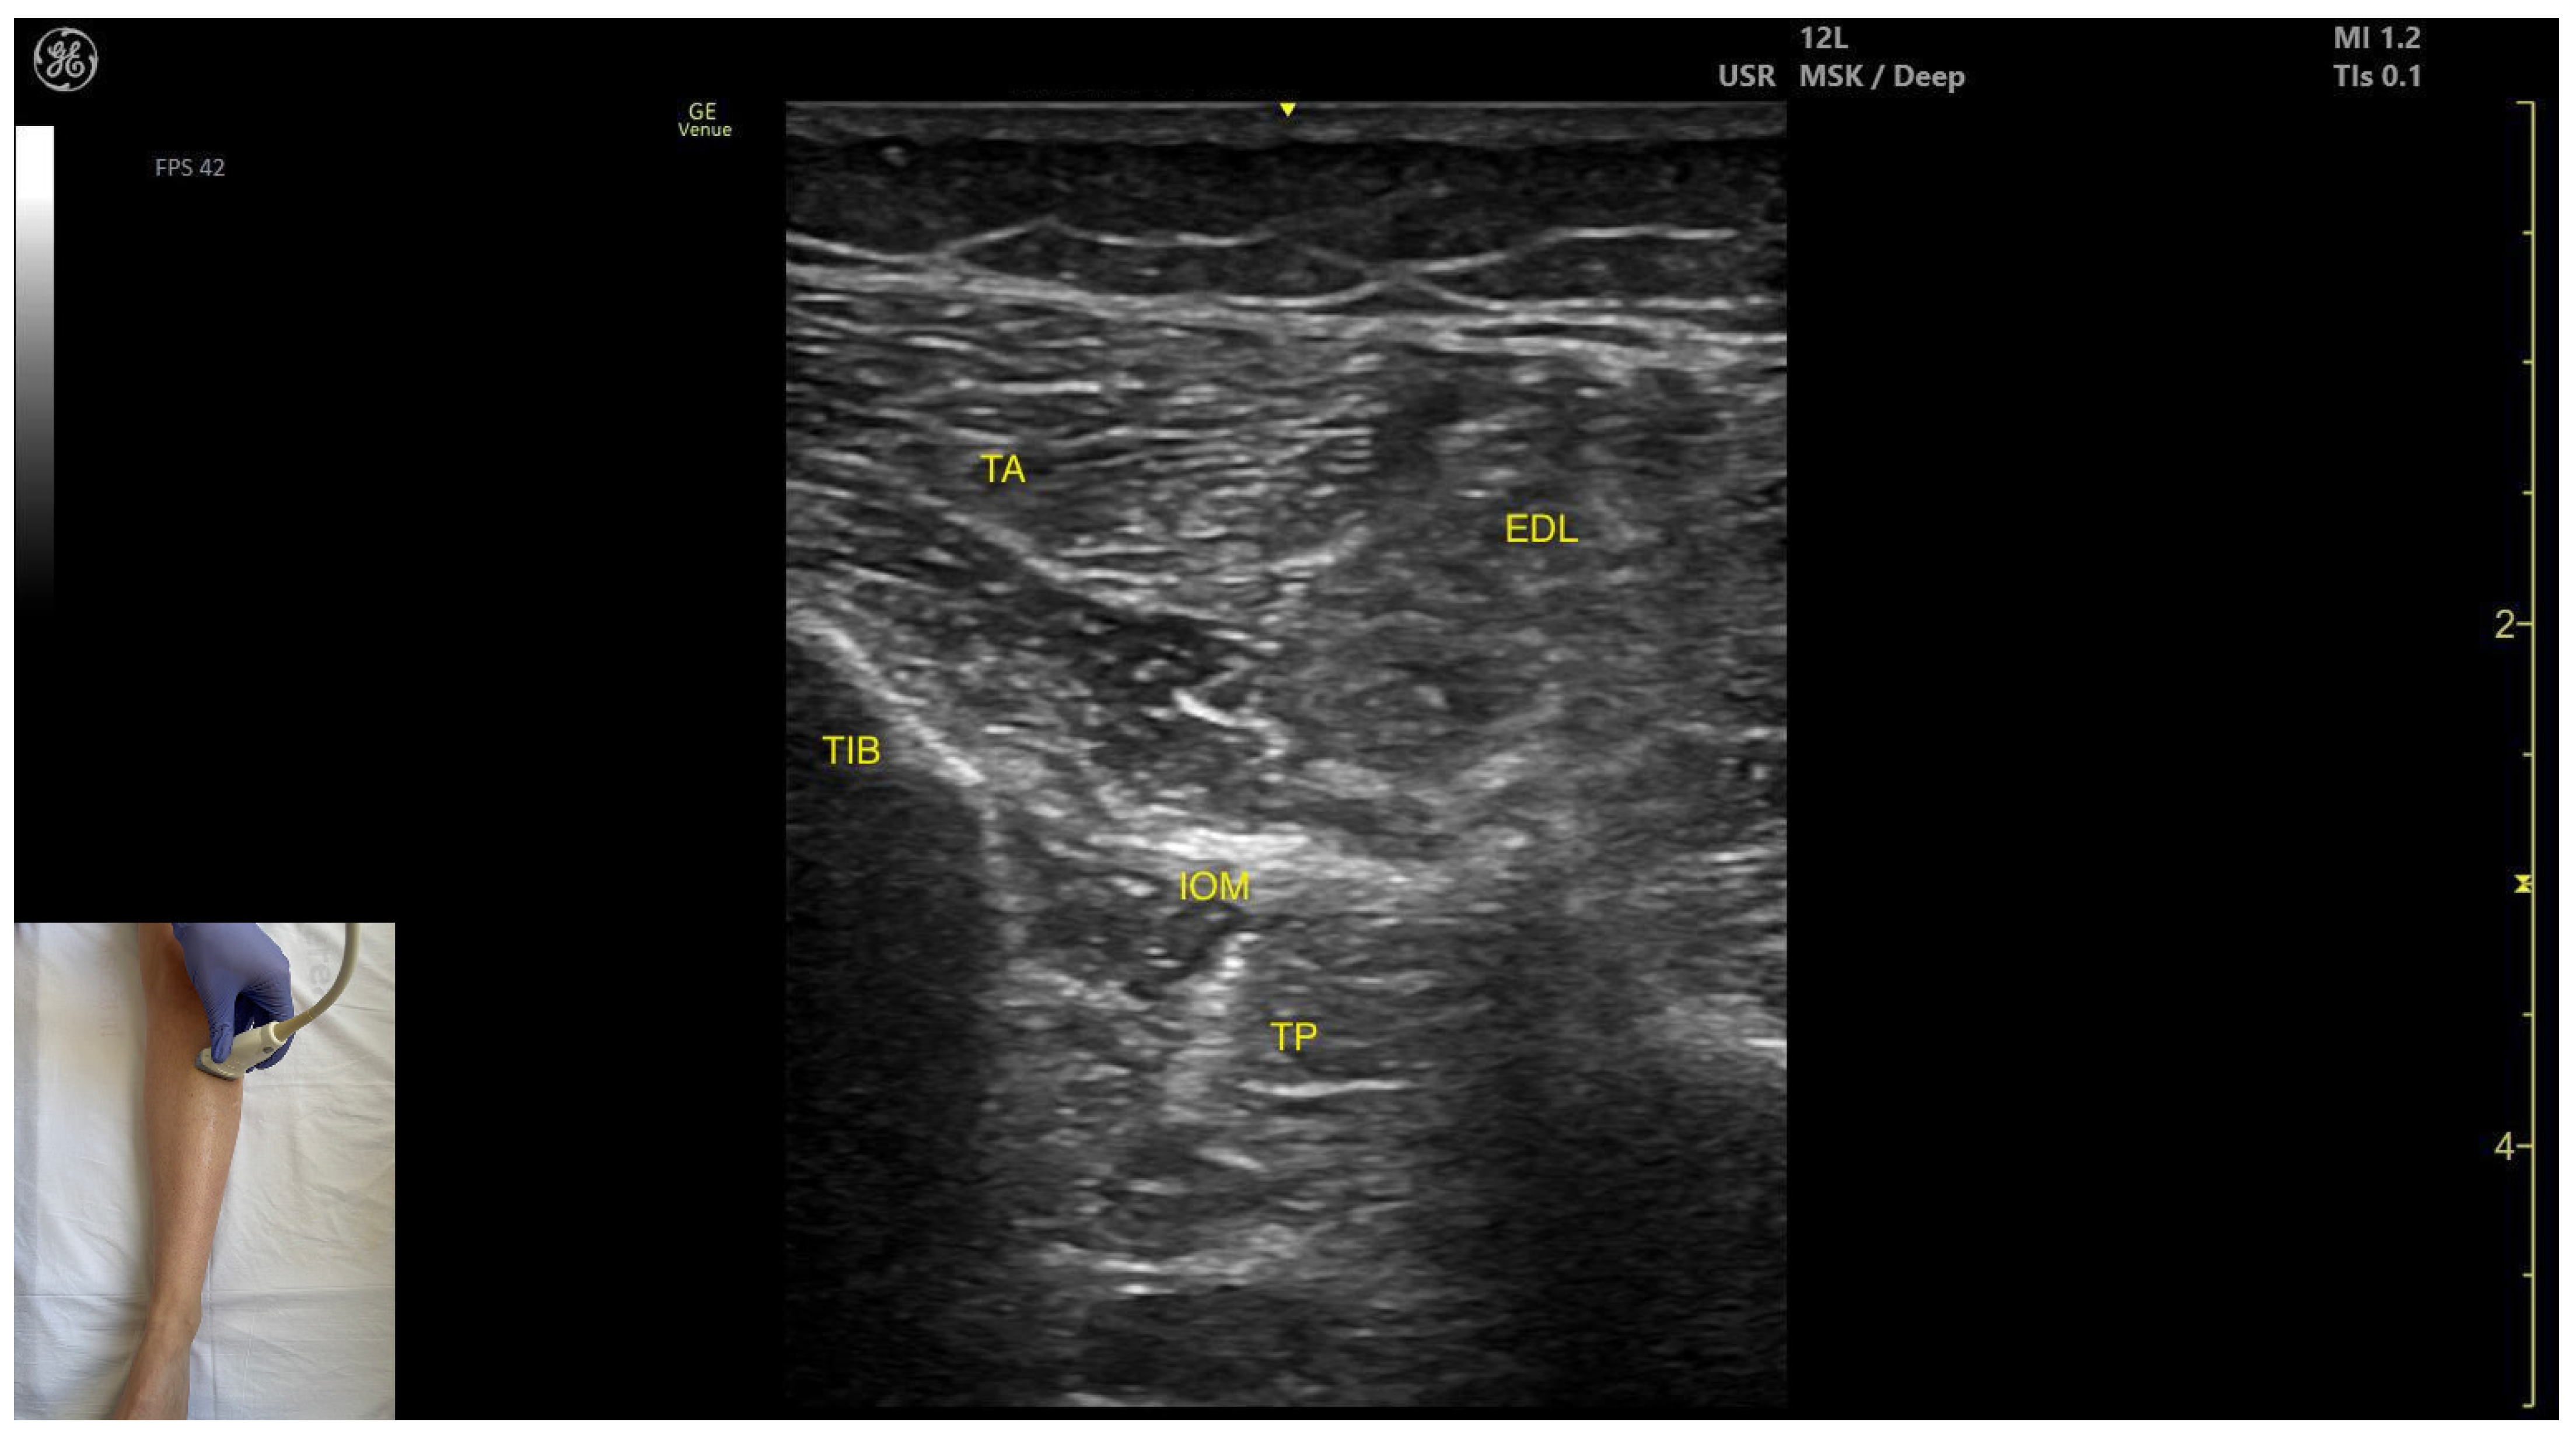

3.3.2. Anterior Window

Ultrasound Identification

Key Ultrasound Landmarks

- Muscle position: It is the deepest muscle in the posterior compartment of the leg.

- Neurovascular bundle: Superficial to the interosseous membrane lies the neurovascular bundle composed of the deep peroneal nerve, anterior tibial artery, and anterior tibial vein.

- External fascia: TP has a pronounced fascia that separates it from the tibialis anterior and extensor digitorum longus during BoNT-A injection.

- Dynamic evaluation: During dynamic evaluation muscle contraction is visible during inversion and plantar flexion of the ankle joint.

- Muscle position: It appears as a superficial muscle mass. Deep to the TA lies the interosseous membrane separating it from the tibialis posterior; the extensor digitorum longus lies lateral to the TA.

- External fascia: The TA does not feature a pronounced fascia that separates it from extensor digitorum longus, during BoNT-A injection.

- Dynamic evaluation: During dynamic evaluation, scanning distally toward the ankle, the tibialis anterior decreases in thickness as it transitions into its tendon. Muscle contraction is seen during plantar dorsiflexion and inversion of the ankle joint.

| Tibialis Posterior (anterior window) | ~10 cm distal to the knee joint, in the lateral portion | Interosseous membrane, deep fibular nerve, anterior tibial artery, and anterior tibial vein (superficial); tibialis anterior (superficial and medial), extensor digitorum longus (superficial and lateral); | Transverse scan on the anterior aspect of the leg | Avoid neurovascular injury |